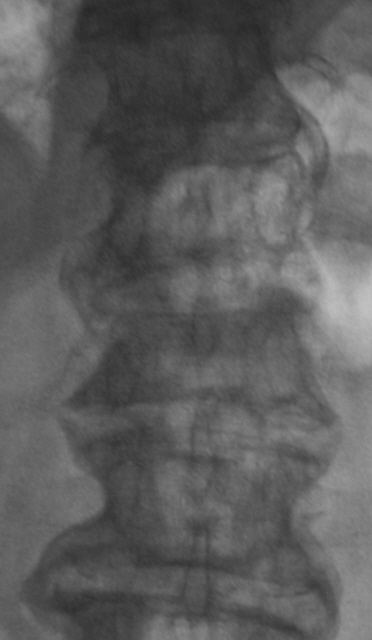

Позвонили из хирургического отделения, чтобы на передвижном аппарате (предназначен только для снятия конечностей) произвели рентгенограммы "грудного отдела позвоночника". Так как, что-то не нравится неврологу. Пациент находится в отделение с диагнозом "Кишечное кровотечение"...

Коллегам было разъяснено "где зад, а где перед", а также для чего нужен передвижной аппарат, и с учетом состояния пациента было предложено доставить в рентгеновский кабинет для полноценного рентгенологического исследования. С пациентом поговорил что болит и когда заболело. Пациент (весьма преклонного возраста мужчина) поведал, что месяц тому упал, и потом отказали ноги. произвели исследование - рентгенографию, "подключили" линейную томографию.

L1 сломал недавно, а L4 - давно

Да. Л1, по всей видимости, и сломали 1 месяц тому.

перелом Л1. Деформирующий спондилёз поясничного отдела позвоночника.